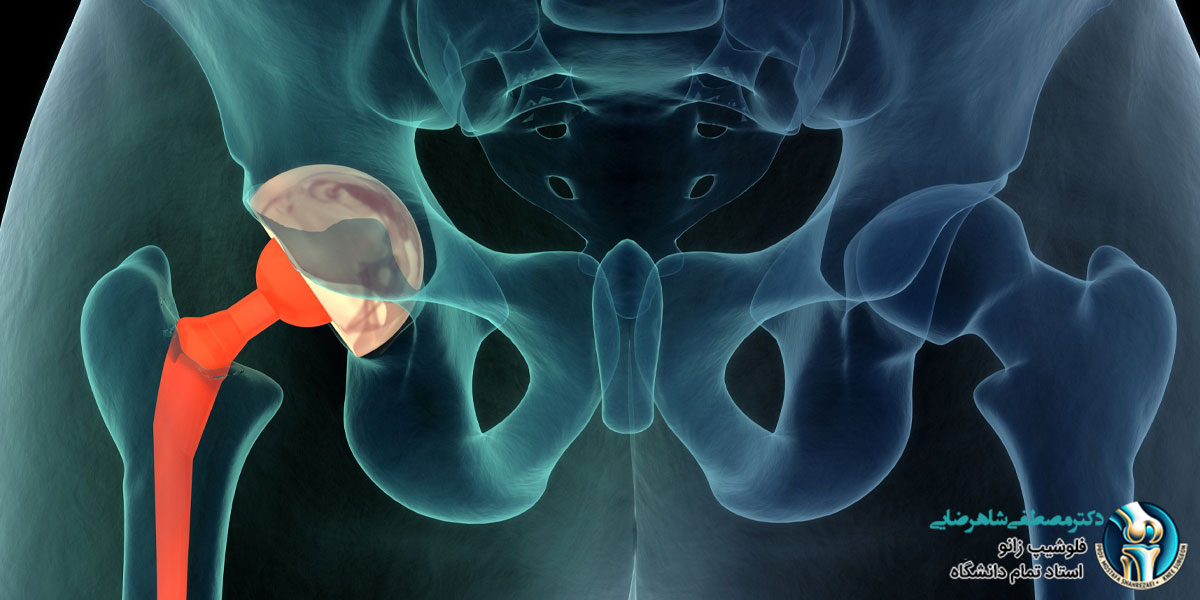

پروتز لگن یک وسیله پزشکی است که جایگزین مفصل لگن آسیب دیده می شود و به افراد کمک می کند تا درد لگن کاهش پیدا کند و راحت تر راه بروند یا فعالیت های روزمره شان را انجام دهند. این پروتزها معمولا برای افرادی استفاده می شوند که به دلیل آرتروز، شکستگی یا آسیب های دیگر مفصل لگن، مشکلات زیادی دارند و حرکت برایشان سخت شده است. یکی از سوالات رایج بیماران، در ارتباط با عمر پروتز لگن است که در ادامه بررسی می کنیم.

مراجعه به پزشک برای برای بررسی عمر پروتز لگن

برای اینکه متوجه شوید پروتز لگن شما در چه شرایطی است و نیاز به تعویض دارد یا خیر، بسیار مهم است که به یک پزشک متخصص مراجعه کنید. دکتر مصطفی شاهرضایی، جراح زانو و استاد دانشگاه با سال ها تجربه در درمان مشکلات لگن و زانو، می توانند به شما کمک کنند تا عمر پروتز لگنتان بررسی و هر گونه نگرانی در این زمینه برطرف شود. ایشان با بررسی دقیق و معاینه کامل، وضعیت مفصل شما را ارزیابی کرده و بهترین راهکار درمانی را متناسب با شرایط شما پیشنهاد می دهند. اگر مشکلاتی مانند درد، سفتی یا محدودیت در حرکت لگن دارید، دکتر شاهرضایی می توانند به شما کمک کنند تا دلیل آن مشخص شود و درمان لازم را شروع کنید. برای دریافت اطلاعات دقیق تر، می توانید با مطب دکتر شاهرضایی تماس بگیرید و وقت مشاوره خود را ثبت کنید.